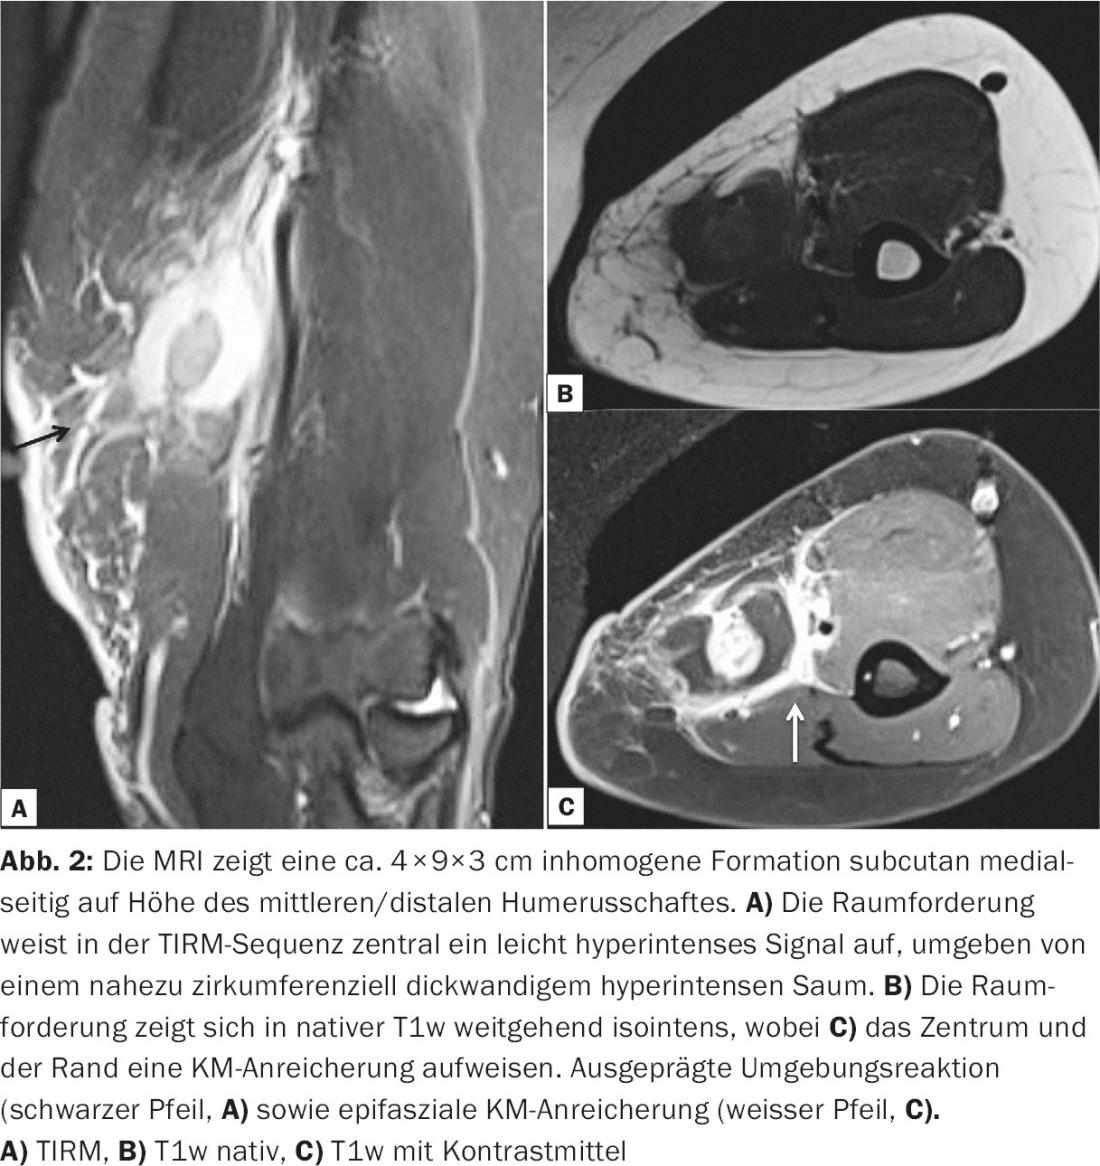

La risonanza magnetica conferma una massa sottocutanea disomogenea, parzialmente KM-affine (Fig. 2).

- Radiologia Ospedale Universitario di Basilea, per gentile concessione del Dr. Garcia Alzamora Meritxell, Vice Primario di Radiologia. Medico Senior Diagnostica Muscoloscheletrica, Ospedale Universitario di Basilea, Dipartimento di Radiologia e Medicina Nucleare.